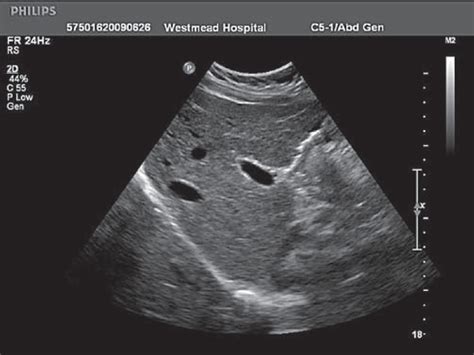

Diagnosing disorders of the Liver Caudate Lobe involves a combination of imaging techniques and laboratory tests. Imaging studies such as ultrasound, computed tomography (CT), and magnetic resonance imaging (MRI) can provide detailed visualizations of the liver and its lobes. These imaging techniques can help identify abnormalities, such as tumors or cysts, in the Liver Caudate Lobe.

Laboratory tests, including liver function tests and blood tests, can also provide valuable information about the health of the Liver Caudate Lobe. Elevated levels of liver enzymes, such as alanine aminotransferase (ALT) and aspartate aminotransferase (AST), may indicate liver damage or disease. Blood tests can also detect the presence of specific markers associated with liver cancer or other conditions.